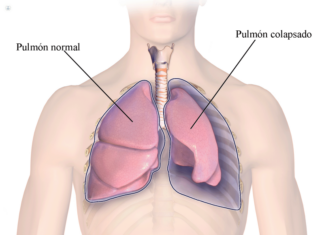

Neumotórax ¿Qué es?